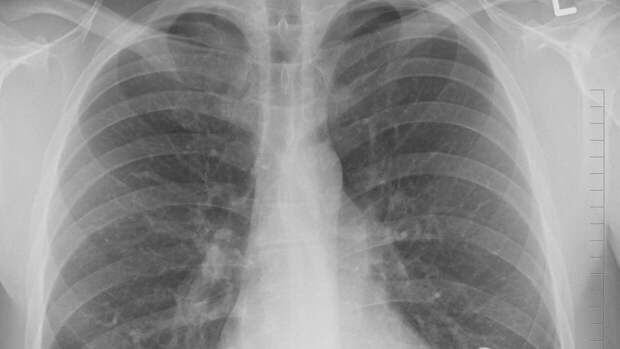

Онкологи установили главные симптомы развития рака легких

Онколог Андрей Пылев назвал основные симптомы рака легких. К числу нетипичных признаков относится удлинение фалангов пальцев.

Исходя из данных Фонда Роя Кастла, одним из симптомов онкологических заболеваний является постепенное увеличение фалангов пальцев и изменение формы ногтевых пластин, пишет iReactor. Изначально, кожа у ногтей начинает блестеть, при этом ногтевая пластина размягчается и ногти выгибаются, а кончики пальцев утолщаются.

В конце концов, изменения можно перепутать с артритом, ведь на запястьях и фалангах появляются дополнительные костные образования. Такие симптомы обычно есть у людей с болезнями сердца и печени, но чаще всего это говорит об онкологии легких. При этом часто наблюдается отдышка, отсутствие аппетита, потеря веса, утомляемость, кашель.

Андрей Пылев, главврач Европейской клиники хирургии и онкологии, отметил, что рекомендуется обращать внимание на повышение утомляемости, отдышку и снижение веса. При этом оговорившись, что некоторые симптомы не проявляются в принципе.